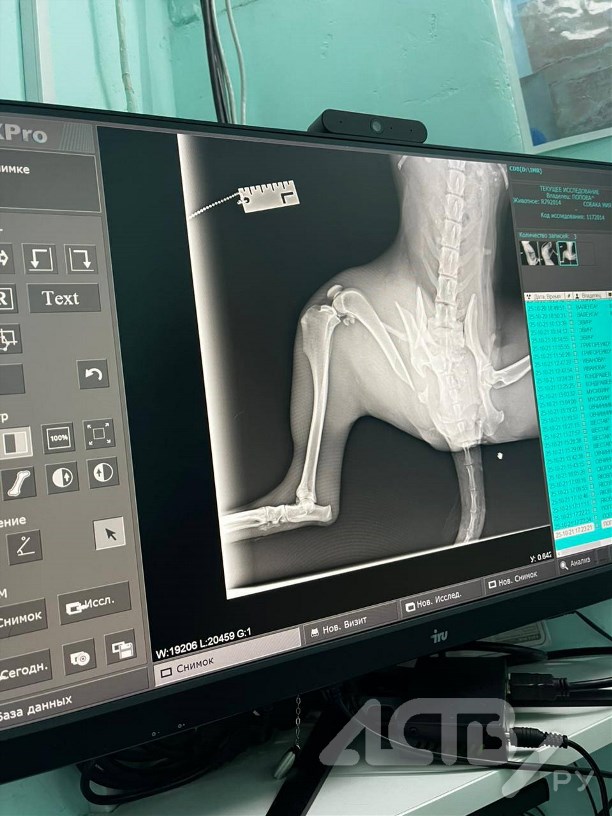

Обследование показало перелом бедренной кости со смещением, переломы костей таза. Требуется дорогостоящая операция, дату которой специалисты назовут уже в ближайшие дни.